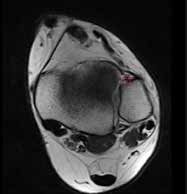

Die Diagnose einer OSG-Distorsion, die später als Grundlage einer adäquaten Therapie dient, ergibt sich aus der Kombination von Befunden verschiedener diagnostischer Ebenen (Anamnese, klinische Untersuchung, bildgebende Diagnostik). Die Erstdiagnostik nach dem Unfall beinhaltet Röntgenaufnahmen des OSG in zwei Ebenen. Im Verlauf und bei persistierenden Beschwerden können MRT- (Abb. 2) oder CT-Aufnahmen angefertigt werden, um Begleitverletzungen wie osteochondrale Frakturen (Abb. 3a), Syndesmosenverletzung oder Peronealsehnenaffektion (Abb. 3b) nachzuweisen.